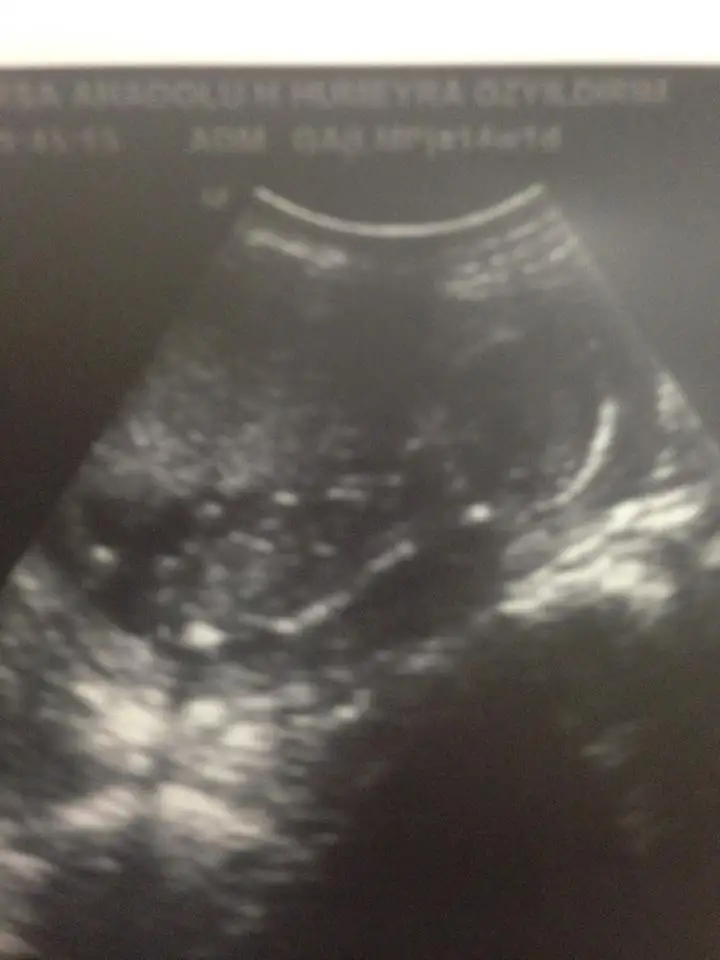

KIZLAR EN SON GÖRÜNTÜMÜZ BUYDU BAŞKA YORUM YAPMAK İSTEYEN VAR MI CİNSİYET TAHMİNİ İÇİN ÇARŞAMBA KONTROLÜM VAR HAKKIMIZDA HAYIRLISI BAKALIM ÇOK HEYCANLIYIM

Eklentiler

• 1.webp

1.webp

15 KB · Görüntüleme: 104